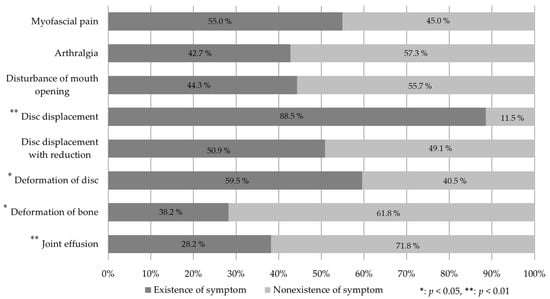

The difference in synovial fluid in joint effusion, according to the duration of manifestation, is shown in Figure 3. The median value for manifestation duration in Grade 0 (no fluid) was four months; in Grade 1 (fluid with punctiform or filamentous), it was one month; in Grade 2 (fluid with cingulate), it was three months; and in Grade 3 (fluid with plenitude), it was two months. There were statistically significant differences between Grade 0 and Grade 1 (p < 0.05), and Grade 0 and Grade 3 (p < 0.05), concerning the duration of manifestation. The amount of synovial fluid in joint effusion observed in MR images was greater for shorter manifestation durations.

Figure 3.

Amount of synovial fluid on joint effusion by the duration from the manifestation.

The amount of synovial fluid in joint effusion was investigated as the hyperintense area of the superior or inferior articular cavities in T2-emphasized MR images, and the amount of synovial fluid in joint effusion was classified from no fluid (Grade 0) to fluid with plenitude (Grade 3). The differences in the grade of joint effusion vs. manifestation duration were analyzed to clarify the timing of joint effusion appearance. The results indicated that the duration of manifestation was longest in TMJs with no fluid on the superior or inferior articular cavities compared to that with fluid with punctiform or filamentous and fluid with plenitude on the superior or inferior articular cavities. Namely, the amount of synovial fluid in joint effusion differed with manifestation duration. The amount of synovial fluid in joint effusion was larger when the manifestation duration was short. This result suggested that joint effusion reflects the inflammation of the articular cavities in the early stages.